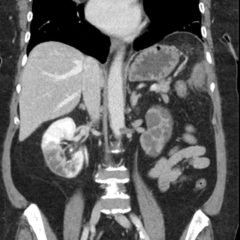

The MRI showed extensive spondylotic changes suggestive of malignancy (red arrows) with severe spinal canal stenosis at the lumbar spine L3-L4 (purple arrows) level contributing to clumping of cauda equina nerve roots and severe bilateral neuroforaminal narrowing with diffuse disc bulges abutting the exiting nerve roots at multiple levels. Findings also showed a hypo-attenuated tumor (blue arrow) and hyper-attenuated loculated tumor (green arrow) consistent with renal cell carcinoma (RCC).